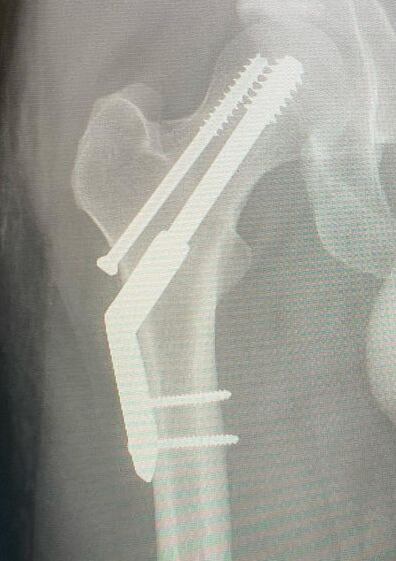

Luego de que Kevin Parker sufrió de una fractura de cadera después de intentar correr un maratón, aunque suene insólito.

Por lo que Kevin Parker -de 37 años de edad- tuvo que ser intervenido de emergencia y ya se encuentra en recuperación.